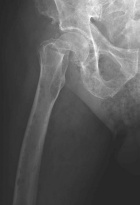

81 year old male status post fall with right hip pain

Zoom image: Radiological image Radiological image.